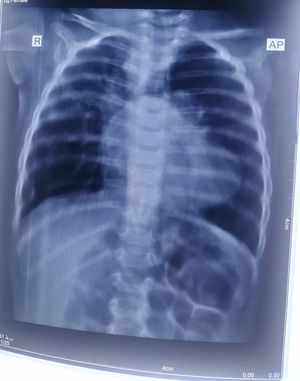

Dr.Rahimi

Is

Dx

What

Cardiomegaly???